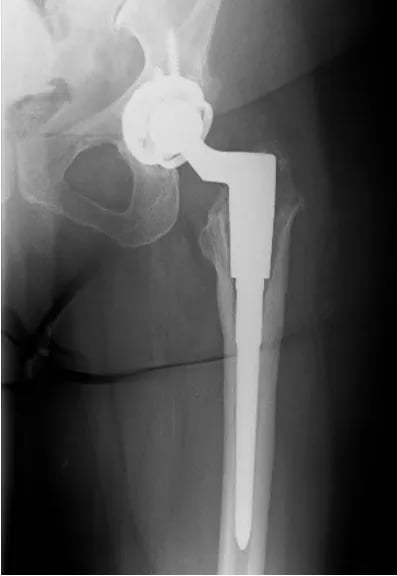

No caso de haver apenas desgaste do polietileno, sem soltura da prótese, deve ser feita uma cirurgia para troca do polietileno, uma vez que a persistência do desgaste pode levar a um processo de soltura com perda óssea, situação que deve ser evitada. Essa cirurgia é mais simples, sem haver necessidade de troca dos componentes de titânio, que permanecem fixos (integrados) ao osso do paciente. Já no caso de soltura, os componentes soltos devem ser removidos e substituídos por outros componentes, geralmente de maior tamanho, para uma adequada fixação num local onde houve perda óssea. Essa cirurgia é chamada de Revisão de Prótese de Quadril.

Para esses casos foram desenvolvidos implantes com revestimento em metal trabecular, que tem uma porosidade muito semelhante à do nosso osso, aumentando ainda mais a capacidade de fixação da prótese ao osso do paciente.

Essa cirurgia geralmente demora mais do que a colocação da primeira prótese e também possui uma recuperação mais lenta. Entretanto, seu resultado é bom, devolvendo novamente a qualidade de vida ao paciente após a recuperação.